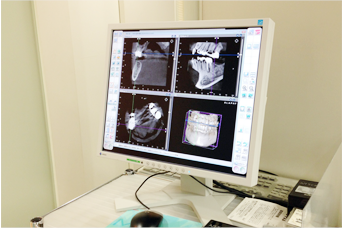

CTスキャンしたお客様の歯の状態のデータを専用のCAD(3D)ソフトで作成し、

コンピュータ上でインプラント治療のシミュレーションを行います。

それにより、事前にインプラントを入れる位置を決めることができ、

より安心安全に外科処置を行う事も可能になります。

歯科用のCTスキャン装置は、従来の機器よりも放射線量が少なく安全に診断を行えます。

自分の歯や骨の状態を、3D画像で立体的に見ることができるので、詳細な診査、診断が可能になります。

正確な診断と安全確実な治療のために歯を支えている周りの骨の状態を知ることは大切なことです。

これからのインプラント治療にCT検査はかかせません。

CT画像は、アゴの骨の立体的な形態や、神経の位置把握、骨密度の診査などに利用されます。

インプラントの治療を行う前だけでなく、治療を終えたあとにも撮影を行って状態を確認します。